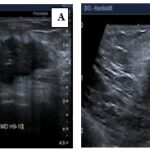

Anexo 2. Imágenes ecográficas del CMTN

Características ecográficas del CMTN

Los resultados de las características ecográficas revelan los siguientes hallazgos en la investigación. Se describe la forma del nódulo de la siguiente manera: en su mayoría es ovalado (n = 13,76%), con márgenes microlobulados (n = 7, lo que corresponde al 41%), seguido de márgenes circunscritos (n = 5, equivalente al 29%). Además, se observa que son hipoecoicos (n = 16, lo que corresponde al 94,2%) y se ubican de manera paralela al eje cutáneo (n = 15, equivalente al 88,2%).

En relación con los hallazgos acústicos posteriores, se destaca que 14 pacientes, que conforman el 82% del grupo, no presentaban hallazgos acústicos ni calcificaciones intra ni extra nodulares.

En cuanto a la vascularización, se observa que en 14 pacientes (equivalente al 82%) no se detectó vascularización en el estudio realizado con Power Doppler. En contraste, 3 pacientes presentaban vascularización periférica, representando el 17,6% de la muestra. En ninguno de los casos se informó distorsión arquitectural ni cambios cutáneos. Sin embargo, en 15 pacientes se observaron adenopatías axilares, lo que corresponde al 88,2% del grupo estudiado.

Los hallazgos radiológicos, tanto en mamografía como en ecografía, describen características comunes de los nódulos en pacientes con CMTN, incluyendo la forma ovalada, los márgenes circunscritos o lobulados, la hipoecogenicidad y la ausencia de hallazgos acústicos posteriores. Estos resultados subrayan la importancia de la evaluación exhaustiva de las características mamográficas y ecográficas en el diagnóstico y la estratificación de los CMTN, que presentan concordancia con lo descrito en la bibliografía médica actual revisada.

Los hallazgos imagenológicos en mamografías, ecografías y resonancias magnéticas en pacientes con CMTN concuerdan con la bibliografía médica actual, lo que respalda la utilidad de estas técnicas para el diagnóstico y caracterización de los CMTN.